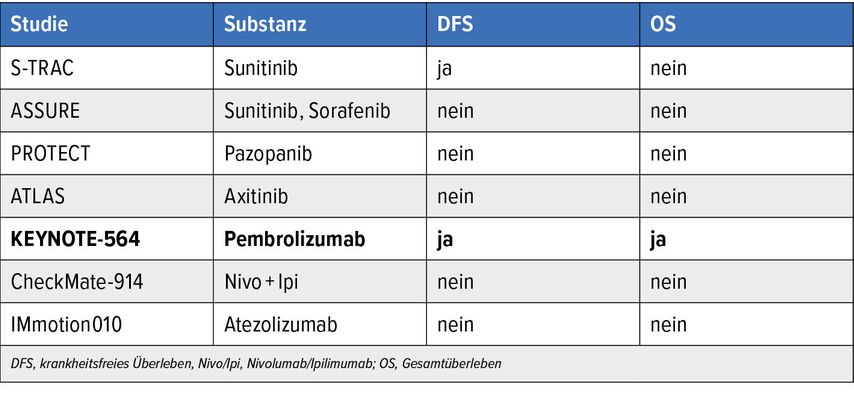

Die chirurgische Entfernung des Tumors gilt als Therapie der Wahl. Für Patient:innen mit hohem Rezidivrisiko nach der Operation ist eine adjuvante Therapie mit dem PD-1-Checkpoint-Inhibitor Pembrolizumab über max. 17 Zyklen (=1 Jahr) zugelassen: Die Zulassung basiert auf signifikanten Verlängerungen im krankheitsfreien Überleben mit einer Reduktion des Risikos für ein Rezidiv um 28% und im Gesamtüberleben mit einem Benefit von 5% nach vier Jahren, wie durch eine grosse randomisierte Phase-III-Studie belegt werden konnte. Allerdings traten bei knapp zwei von zehn Patient:innen höhergradige Nebenwirkungen unter der adjuvanten Therapie auf.12

Zwei weitere Studien mit Immuncheckpoint-Inhibitoren (ICI) zeigten hingegen keinen signifikanten Vorteil im DFS und OS. Die Entscheidung für die adjuvante Therapie sollte individuell unter Berücksichtigung des Risikos für das Auftreten eines Rezidivs, des Nebenwirkungsprofils und des Patient:innenwunschs getroffen werden. Patient:innen mit einem sarkomatoiden Anteil in der Histologie und Patient:innen mit einer initialen Oligometastasierung und «no evidence of disease» (NED) nach Resektion des Primarius sowie der Oligometastasen (bis max. 5) sollten bei fehlenden Kontraindikationen zur Durchführung einer adjuvanten Therapie aufgrund des grossen Benefits innerhalb der Subgruppen ermutigt werden. Unklar bleibt derzeit die Therapiesequenz bzw. die Wirksamkeit einer ICI-Therapie bei Auftreten eines Rezidivs nach adjuvanter Pembrolizumab-Therapie.

Tab. 2: Studien zur Adjuvanz bei lokalisiertem ccRCC mit hohem Rezidivrisiko (modifiziert nach den Onkopedia Leitlinien)13

Daten zur adjuvanten Gabe von Pembrolizumab zeigen bei Patient:innen mit ccRCC und hohem Rezidivrisiko nach Resektion im lokalisierten Stadium einen signifikanten Vorteil in DFS und OS.